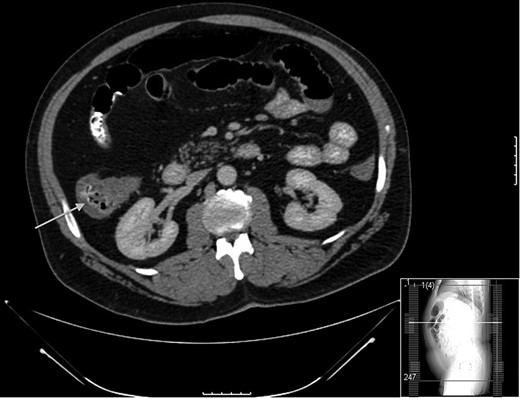

A 52-year-old male with a history of Stage IIIb melanoma initially underwent a wide local excision with a sentinel lymph node biopsy for a 2.1 mm in-depth melanotic lesion of his left upper arm melanoma. The sentinel lymph node biopsy at that time was negative for malignancy. Two years later he returned with an in-transit metastasis proximal to the original lesion. He underwent re-excision and axillary lymph dissection at that time. Following the removal of this lesion he was started on ipilimumab at 6 mg/kg. He had completed two injections spaced 1 month apart before he returning to clinic with complaints of diarrhea and significant abdominal pain. At that time a CT scan (Fig. 1) and colonoscopy with biopsy were performed, both were consistent with active colitis. Adjuvant therapy was suspended and the patient was started on prednisone at standard dosage. The patient’s symptoms improved over the course of the next week. However, 2 weeks following initiation of immunosuppresion he presented acutely to the emergency department with hypotension, peritonitis and free air beneath the diaphragm. He was taken to the operating room for exploratory laparotomy. Following entrance to the abdomen via a midline incision extensive inflammation was noted from the terminal ileum to the mid-transverse colon. Perforation of the cecum was the salient finding (Fig. 2). A right extended hemicolectomy was performed with end ileosotomy. Pathology was consistent with ipilimumab-induced perforation colitis (Fig. 3). The patient tolerated the procedure and was cared for in the surgical intensive care unit overnight before being released to the general surgery floor in the morning. His postoperative course was complicated by continued symptomatic enteritis for the next 2 weeks; however by Week 3 repeat colonoscopy revealed evidence of regeneration and healing of the colonic mucosa. He was discharged home and will likely be scheduled for ileostomy takedown in 6–8 weeks following cessation of immunosuppression.

Cecal perforation identified at the time of operation. Gross inflammation observed from the ileocecal junction to the mid-transverse colon.